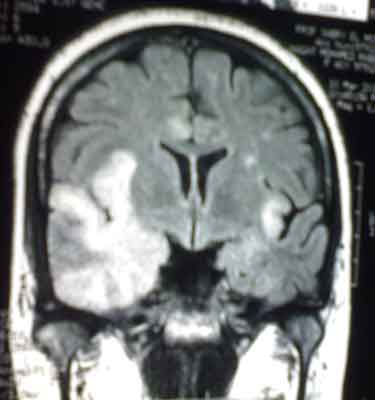

MRI for a female patient aged 41 who presented in a state of disturbed

conscious level which preceded days before by fever, headache,

hallucinations, behavior changes and weakness of lower limbs.

What is the diagnosis?

It is a case of "Herpes Encephalitis". Note

the obvious temporal lobe involvement.

N.B. Herpes simplex encephalitis presents with nonspecific symptoms: a

flu-like prodrome, followed by headache, fever, behavioral and speech

disturbances, and focal or generalized seizures. The temporal lobe is

often involved. Untreated disease and presentation with coma carry a

high mortality rate, with many survivors suffering neurologic sequelae.